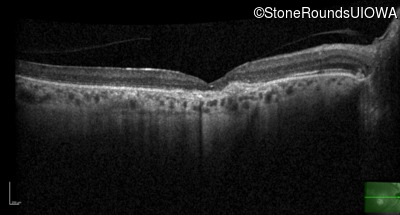

Optical Coherence Tomography - Left - 20/80

Exemplar / OCT Stack

Infrared Fundus Photograph - Right - 20/125 -2